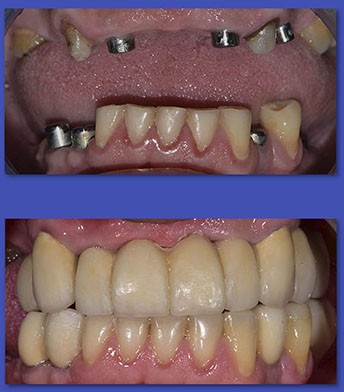

8. IMPLANTES DENTALES

Los Implantes de titanio vienen a ser hoy la mejor forma de recuperar los dientes perdidos. El porcentaje de éxito de los implantes esta cercano al 95%. Los Implantes son una prótesis que se inserta en los huesos maxilares y sobre ellas se pueden realizar rehabilitaciones tanto de uno como de varios dientes.

ANTES

DESPUÉS